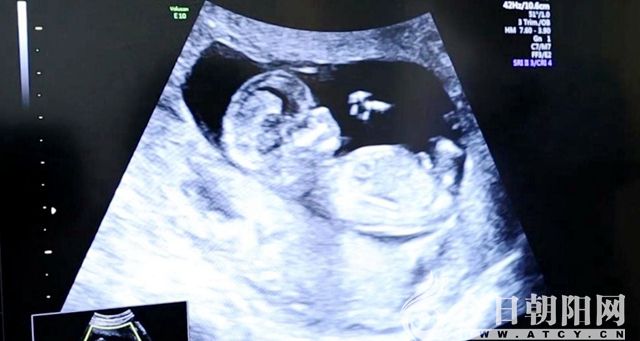

2018年11月,得知家門口的朝陽市中心醫(yī)院開展了“夫精人工授精技術(shù)”,致遠(yuǎn)夫婦便抱著試一試的態(tài)度前來就診。在此之前,夫婦兩人為了能夠生一個健康的寶寶,想盡了辦法,輾轉(zhuǎn)多家醫(yī)院進行檢查、治療,結(jié)果都以失敗告終。通過一段時間的基礎(chǔ)治療,生殖醫(yī)學(xué)中心的醫(yī)生為女方實施了自然周期“夫精宮腔內(nèi)人工授精”。緊接著,好消息接踵而來:2019年1月初,致遠(yuǎn)夫婦來院檢查時,“血清β—HCG”指標(biāo)顯示受孕成功;2月初到院復(fù)查時,他們在超聲影像下看(聽)到了胎兒胎心穩(wěn)健而有力的波動。